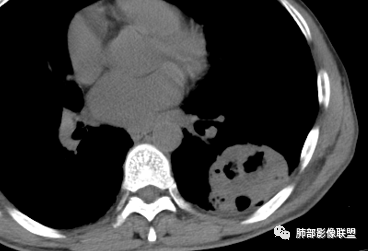

1、老年男性,肺气肿背景,咳嗽胸闷一个月,血象不高,C反应蛋白无明显升高,无发热。

2、左肺下叶近胸膜下较大肿块,土豆样外形,边缘清楚,膨隆分叶,未见明显渗出;病灶内部多坏死及空洞,似鬼脸征,坏死边界不清;增强扫描轻度不均匀环形强化;近端支气管似有阻塞截断。肺门纵隔未见肿大淋巴结。

3、综上所述,考虑恶性,鳞癌可能。

胸CT:肺气肿背景,双肺下叶背侧蜂窝影,左肺下叶肿块影,位于交界地带,边缘清,膨隆、分叶,内有多发厚壁空洞(重叠在蜂窝背景上,不敢确定真实性),洞壁光滑,内有多灶性坏死,支气管在肿物边缘截断,胸膜局部增厚,中度强化。考虑:恶性肿瘤,鳞?肉瘤?鉴别TB、隐球等。